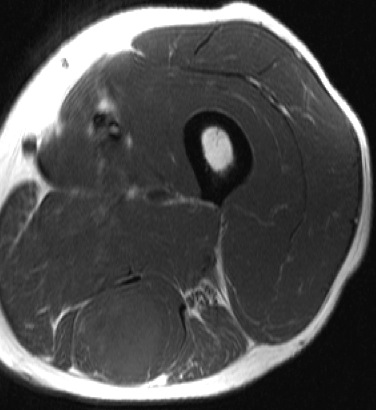

Figure 3 for case Adenocarcinoma lung metastasis

Figure 3